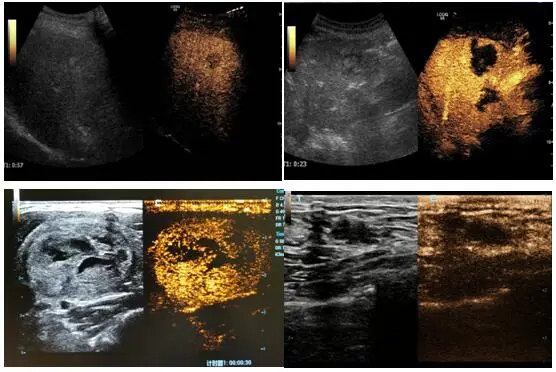

超声造影又称声学造影,是在常规超声检查基础上,通过静脉注射含有气泡的超声造影剂,借助超声造影剂气体微泡在声场中产生的强烈背向散射来获得对比增强图像,是一种可以明显提高超声诊断分辨力、敏感性和特异性的技术。能实时动态观察、定量评估器官、组织及病灶局部的血流灌注信息。使超声检查能够清楚显示微细血管和组织血流灌注,大大提高超声的诊断水平,达到与增强CT扫描媲美。

造影剂经肘静脉注入后能分布于全身组织和脏器的毛细血管,使组织和脏器的超声回声增强至一万倍以上,使原本普通超声下不能发现、不明显或无法明确诊断的病灶变得明显、易见。超声医生根据超声造影特征诊断全身各脏器肿瘤的良、恶性,如:肝癌、肾癌、卵巢癌、肝血管瘤、肾错构瘤等;确定病变的边界及包膜,如:确定肝脓肿病灶边界,肥大肾柱、肾“驼峰”征与肾肿瘤的鉴别等;微小病灶的早期发现,如:直径小于1cm的乳腺癌、鉴别微信病灶是囊性还是实性;观察空腔脏器走形及占位,如:输卵管堵塞、宫腔息肉等;血管斑块、血管堵塞等疾病的诊断;肝、脾、肾等实质脏器外伤的快速诊断;子宫肌瘤、内膜息肉、肝肿瘤、甲状腺肿瘤等实体瘤介入治疗后的疗效评估;心脏功能的准确评估等等,可谓是“全能选手”!